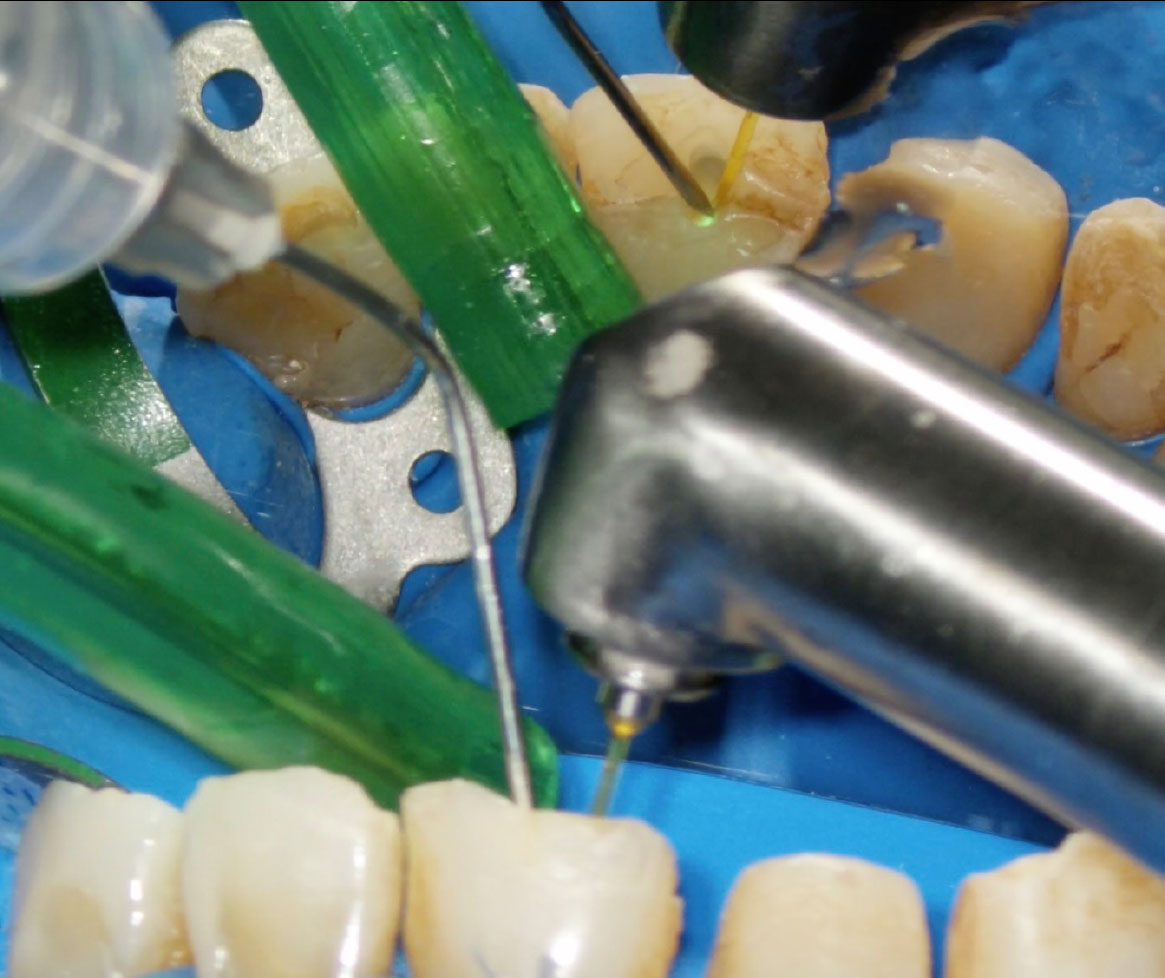

La massima azione microbicida avviene combinando ipoclorito di sodio e laser: una volta inoculato l’ipoclorito all’interno del canale, si porta la fibra (200nm) a circa 1 mm dall’apice (fig. 2), si attiva, quindi, con movimenti circolari in direzione apico-coronale, si percorre il canale in tutta la sua lunghezza. L’operazione, da ripetere tre volte, dura complessivamente 20s e si effettua al termine della fase di strumentazione (fig. 3, 4).

In letteratura, la maggior parte delle ricerche è stata condotta utilizzando come fotosensibilizzanti il blu di metilene (MB), il blu di toluidina (TB) e il verde di indocianina (ICG), per lunghezze d’onda rispettivamente di 660, 635 e 810nm. Le modalità di utilizzo prevedono che la fibra venga portata ad 1mm dall’apice quindi, con movimenti circolari in direzione coronale, si attivi il fotosensibilizzante. (fig. 5).